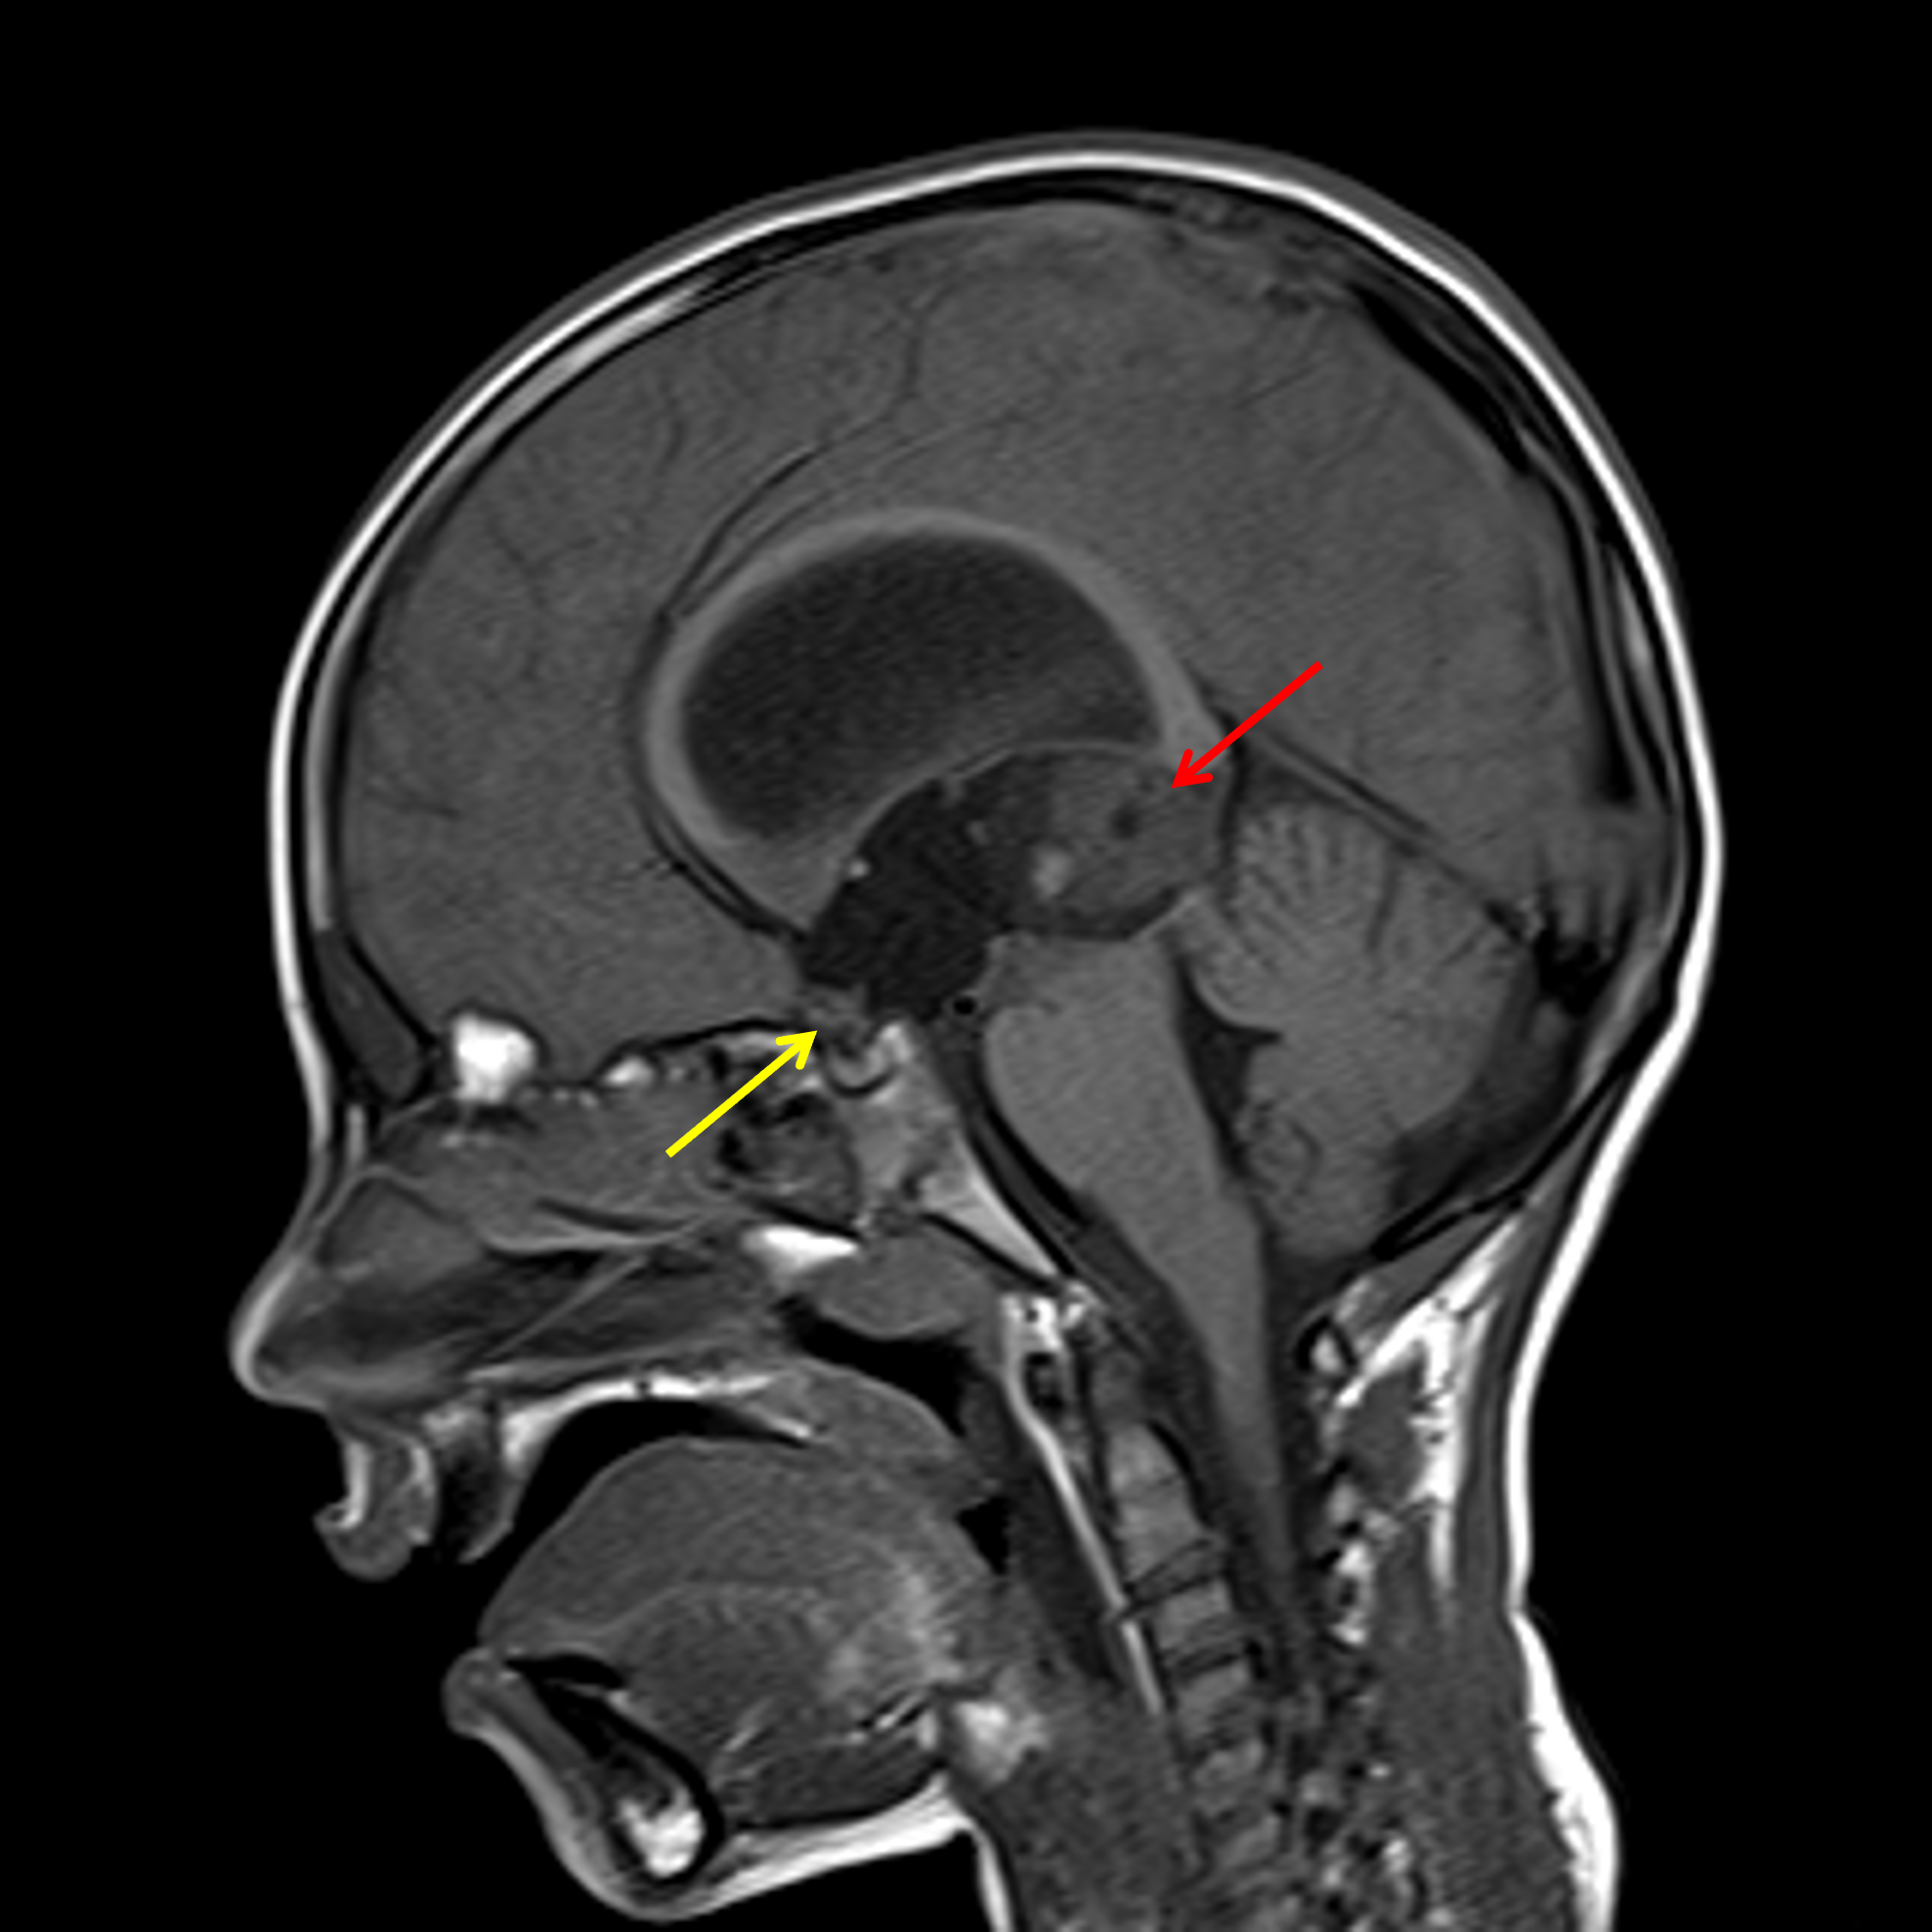

Age: 7

Sex: Male

Indication: Altered mental status

Teratoma (pineal region)